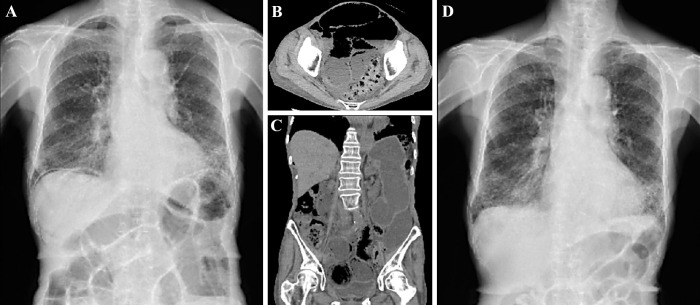

Pneumatosis Intestinalis Induced by Nintedanib.